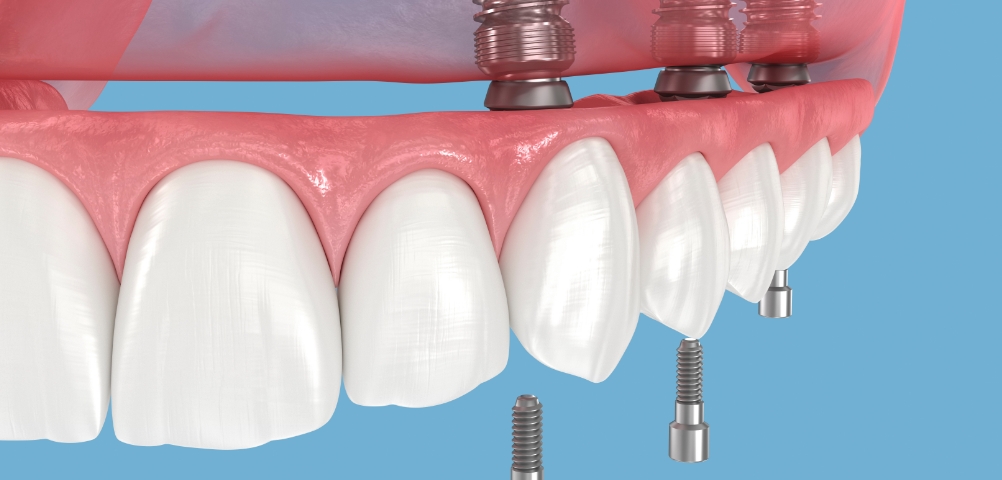

种植牙是在精准诊断与治疗计划的基础上,

通过多个步骤进行的治疗方式

会根据患者的口腔状况, 分阶段安全推进

考虑骨骼状态与神经位置,

制定种植位置与手术计划

根据患者状况,

应用个性化种植牙设计

按照预定导板,

稳定植入种植牙